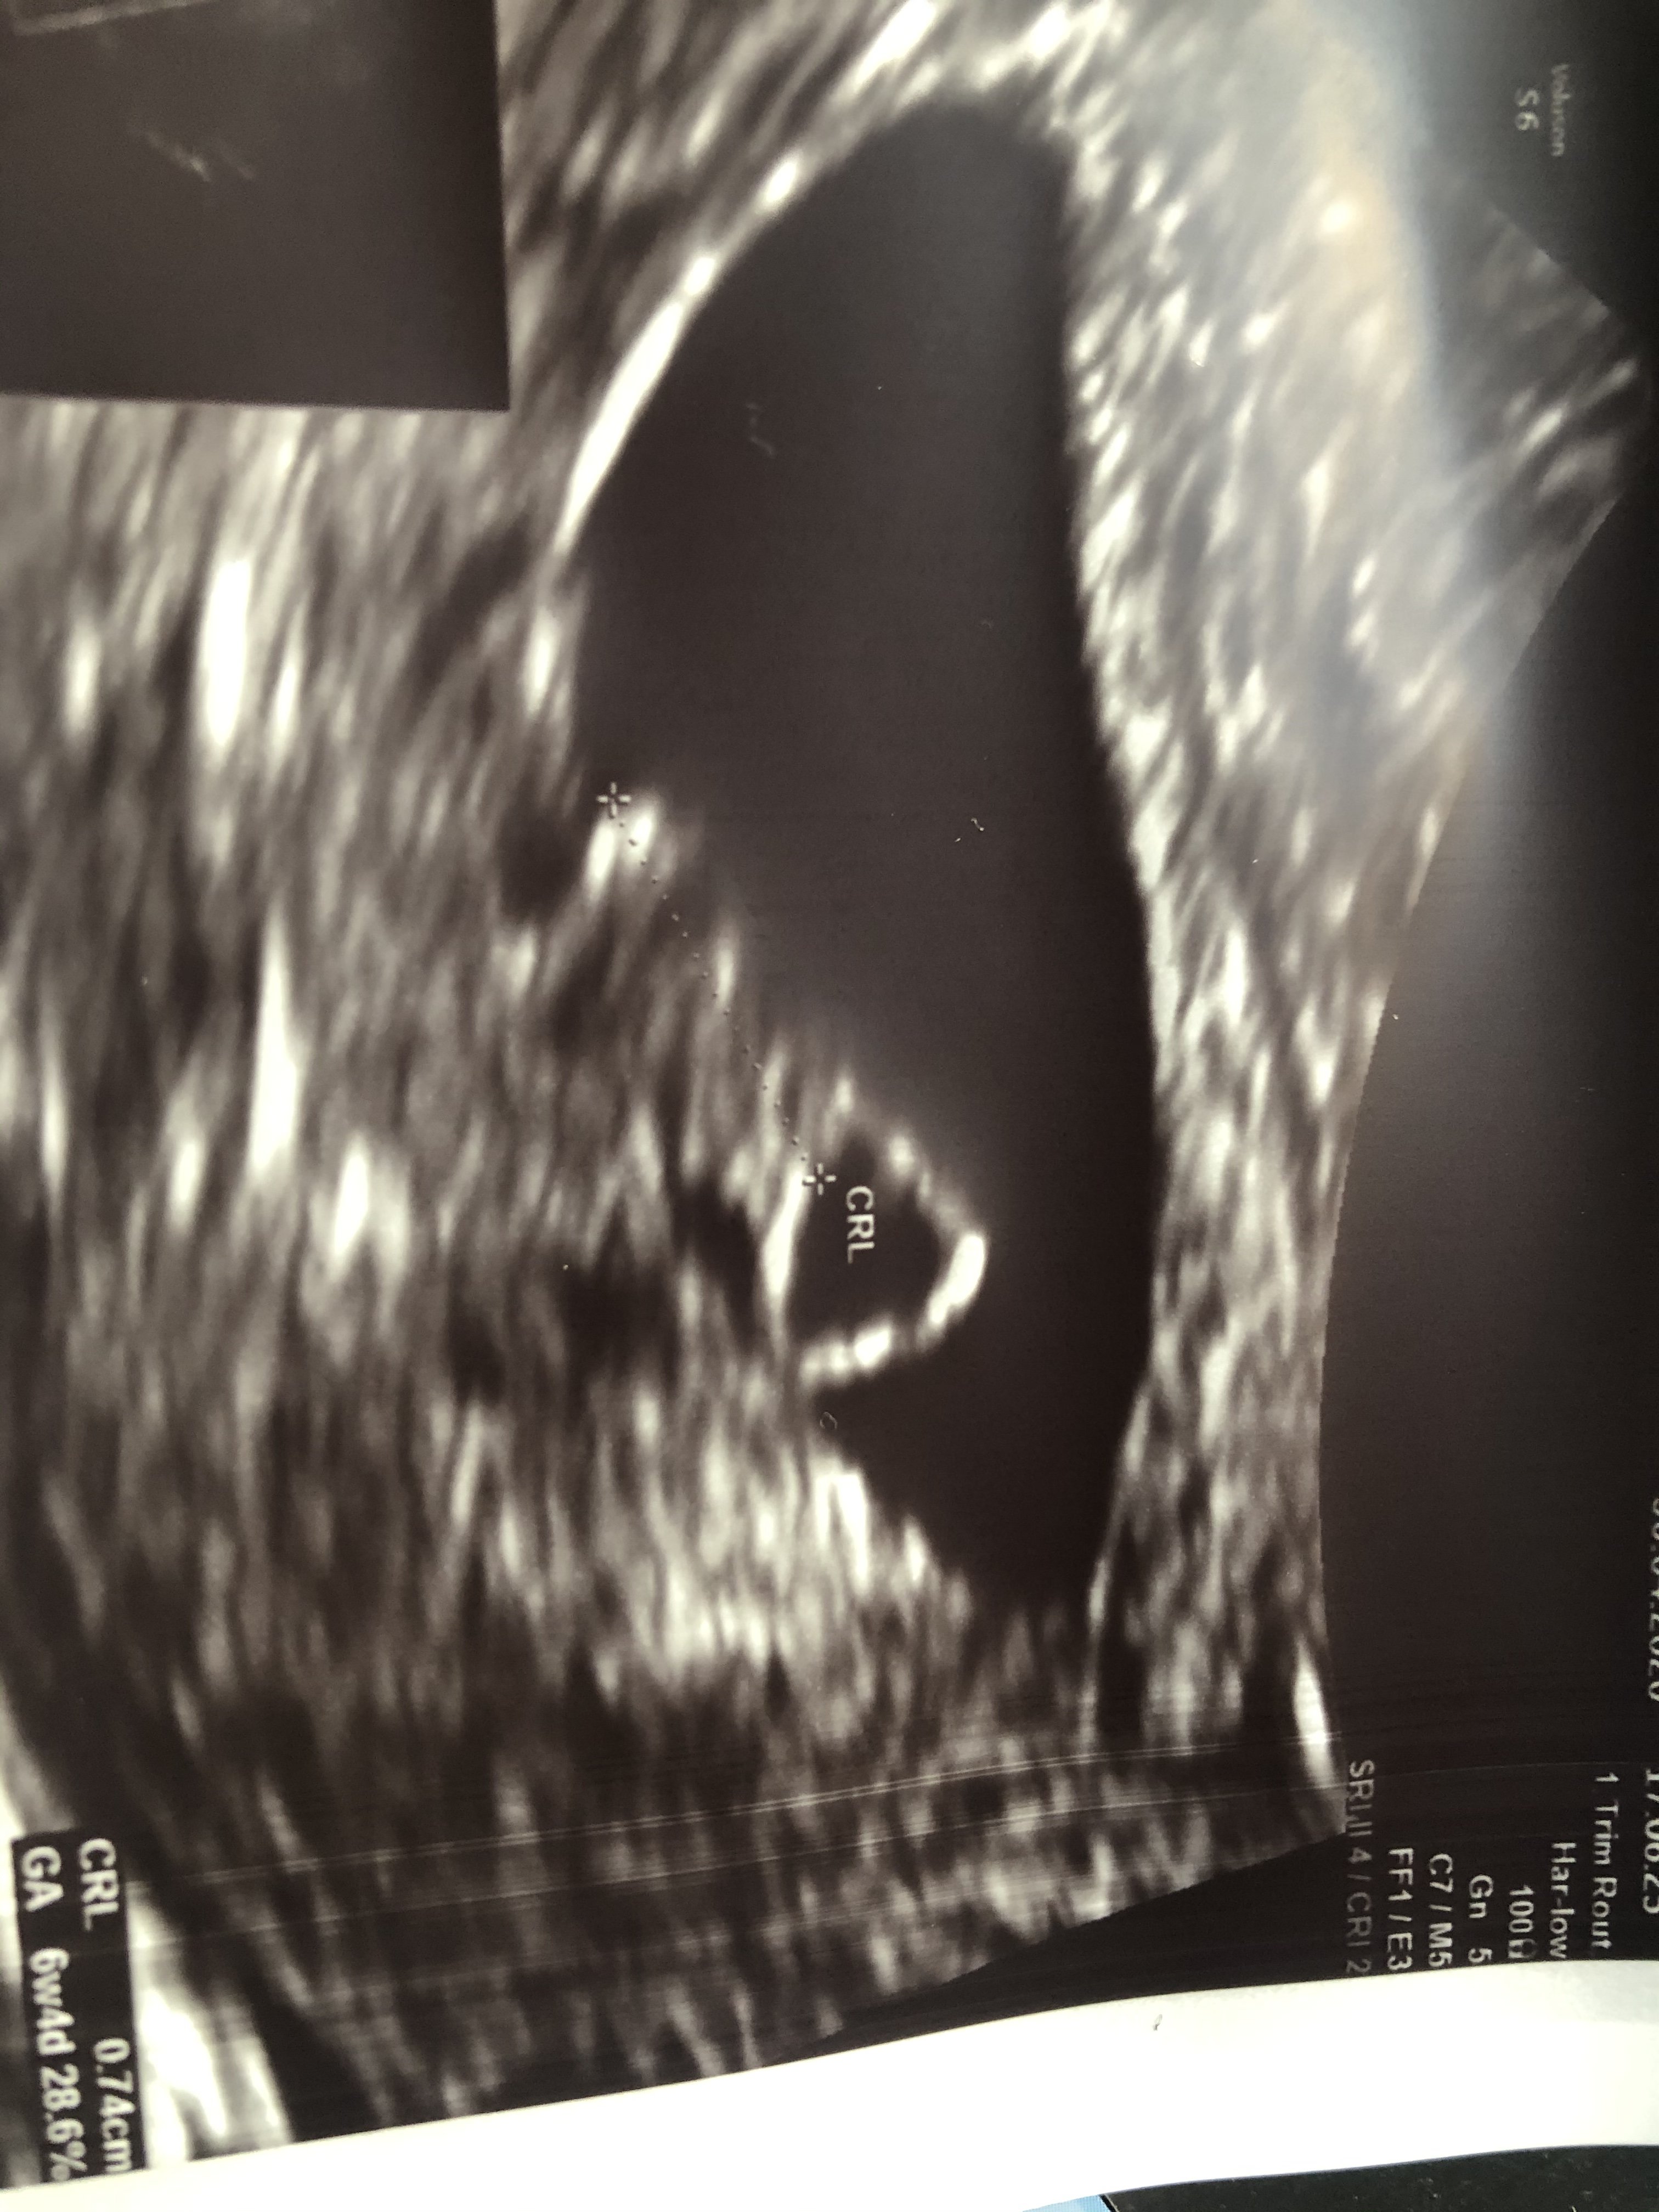

Dziewczyny jestem już po badaniu i wszystko jest dobrze [emoji173]️ jest zarodek i wiek ciąży to 6+1, a wg apki 7+2 [emoji4] jestem mega szczęśliwa i na szczęście narzyczony mógł być ze mną i widział jak serduszko pika [emoji173]️[emoji173]️[emoji173]️ termin również przesunął się z 27/12 na 23/12

Dziewczyny jestem już po badaniu i wszystko jest dobrze ❤️ jest zarodek i wiek ciąży to 6+1, a wg apki 7+2 😊 jestem mega szczęśliwa i na szczęście narzyczony mógł być ze mną i widział jak serduszko pika ❤️❤️❤️ termin również przesunął się z 27/12 na 23/12

podobnie mam 6+4 wg usg (wg apki 7+0), termin na 20.12 (aplikacja liczyła 18.12).

Serducho pikało i słyszałam to najważniejsze ;) następna wizyta 22.05 a Ty kiedy? ;)